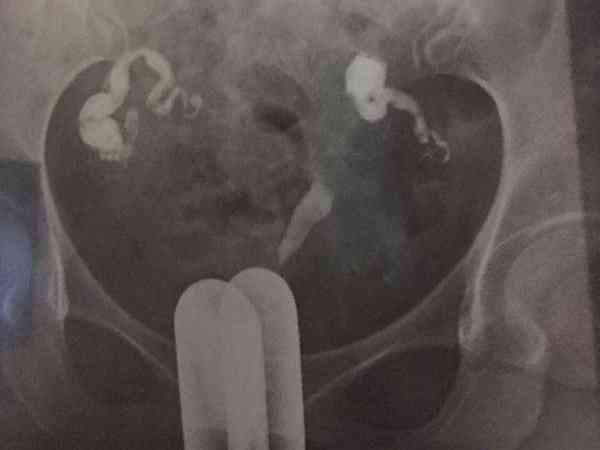

現在檢查雙側輸卵管積水嚴重,準備第二次做試管嬰兒,醫生說我在試管嬰兒移植前需要做結紮手術,請問這個一定要處理嗎?雙側輸卵管積水嚴重的患者,做試管嬰兒在胚胎移植前是一定要處理好積水的,不過不一定就是通過結紮,還可以選擇藥物治療或者是切除輸卵管。藥物治療主要是通過服用阿莫西林、阿奇黴素等抗生素,讓積水慢慢消失,這種方式一般只適用於積水較少的患者。而輸卵管切除適用於情況比較嚴重,沒有自然生育需求的患者。

輸卵管積水指輸卵管傘端阻塞導致輸卵管滲出液積聚形成積液,一般是由於輸卵管炎導致的,如果積水嚴重在試管移植前不做處理,那麼就可能會導致胚胎著床失敗、宮外孕、生化流產等情況,這會直接而影響到輸卵管積水做試管成功率,所以大家在試管移植前一定要做好處理工作,處理方法有以下三種: